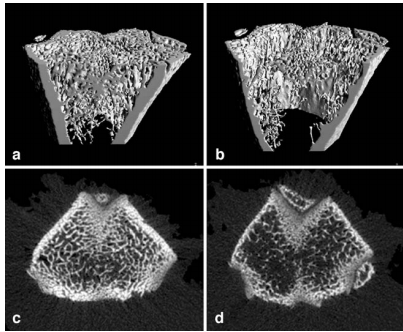

results - microarchitecture significant alterations due to SCI, as shown in Figure. 48% decrease in trabecular BMC, with an associated decrease in Tb.Th and Conn.D (n = 5) compared to control (n = 5). mean cortical bone content decreased by 35%, with a significant decrease in Ct.Th. BS.BC increased in both compartments indicating increased trabecular and cortical bone resoption.